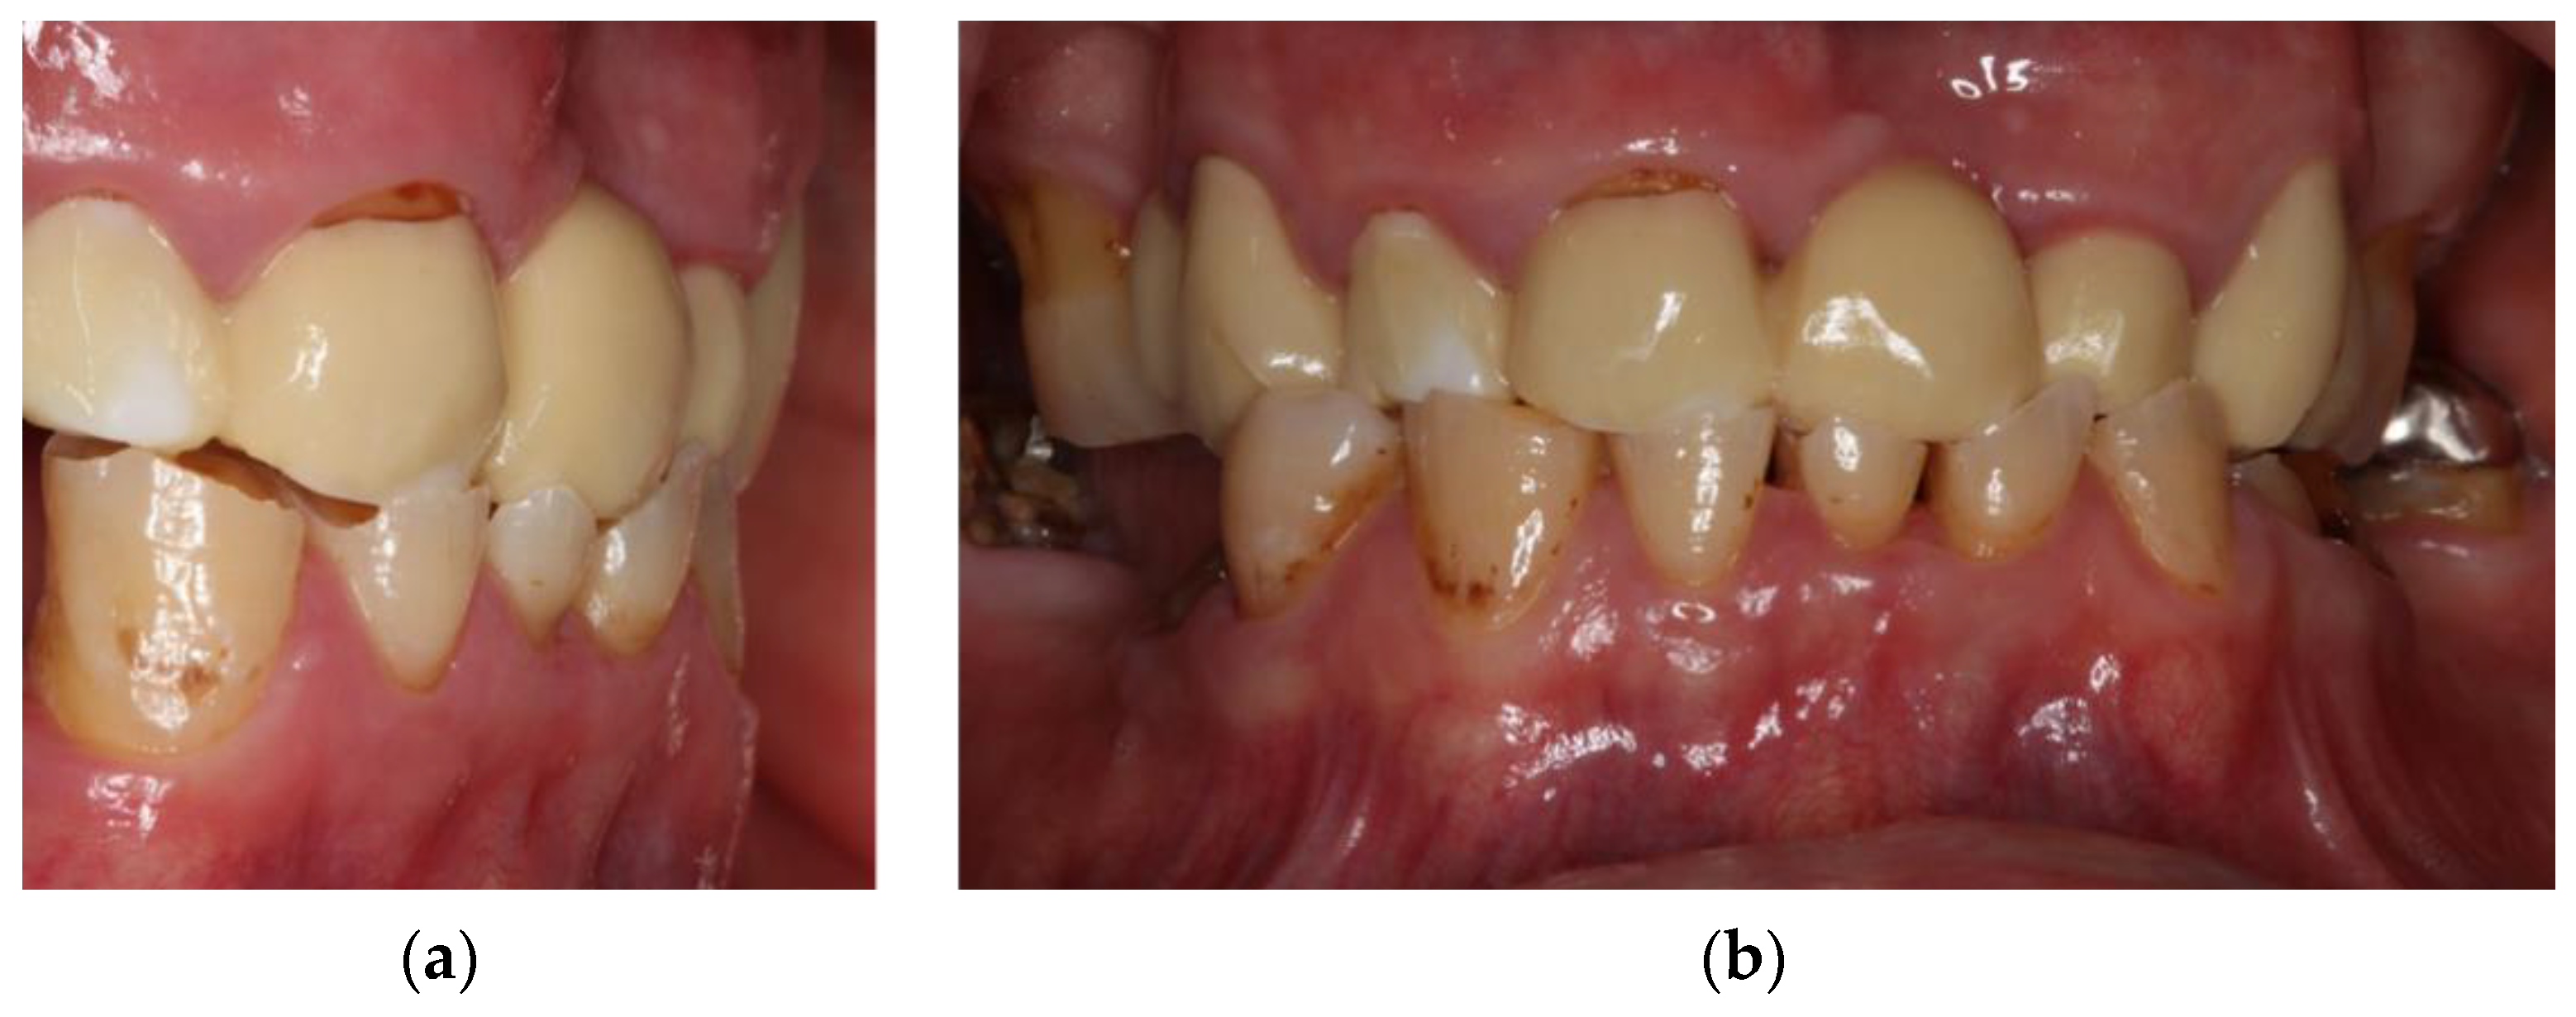

- Locator abutments on both implants, single-crown FDPs on the remaining lower molar teeth, insertion of a tooth-colored and tooth-shaped monolithic RDP fabricated from POM with minimally invasive preparation of the lower anterior teeth (experimental character in long-term endurance).